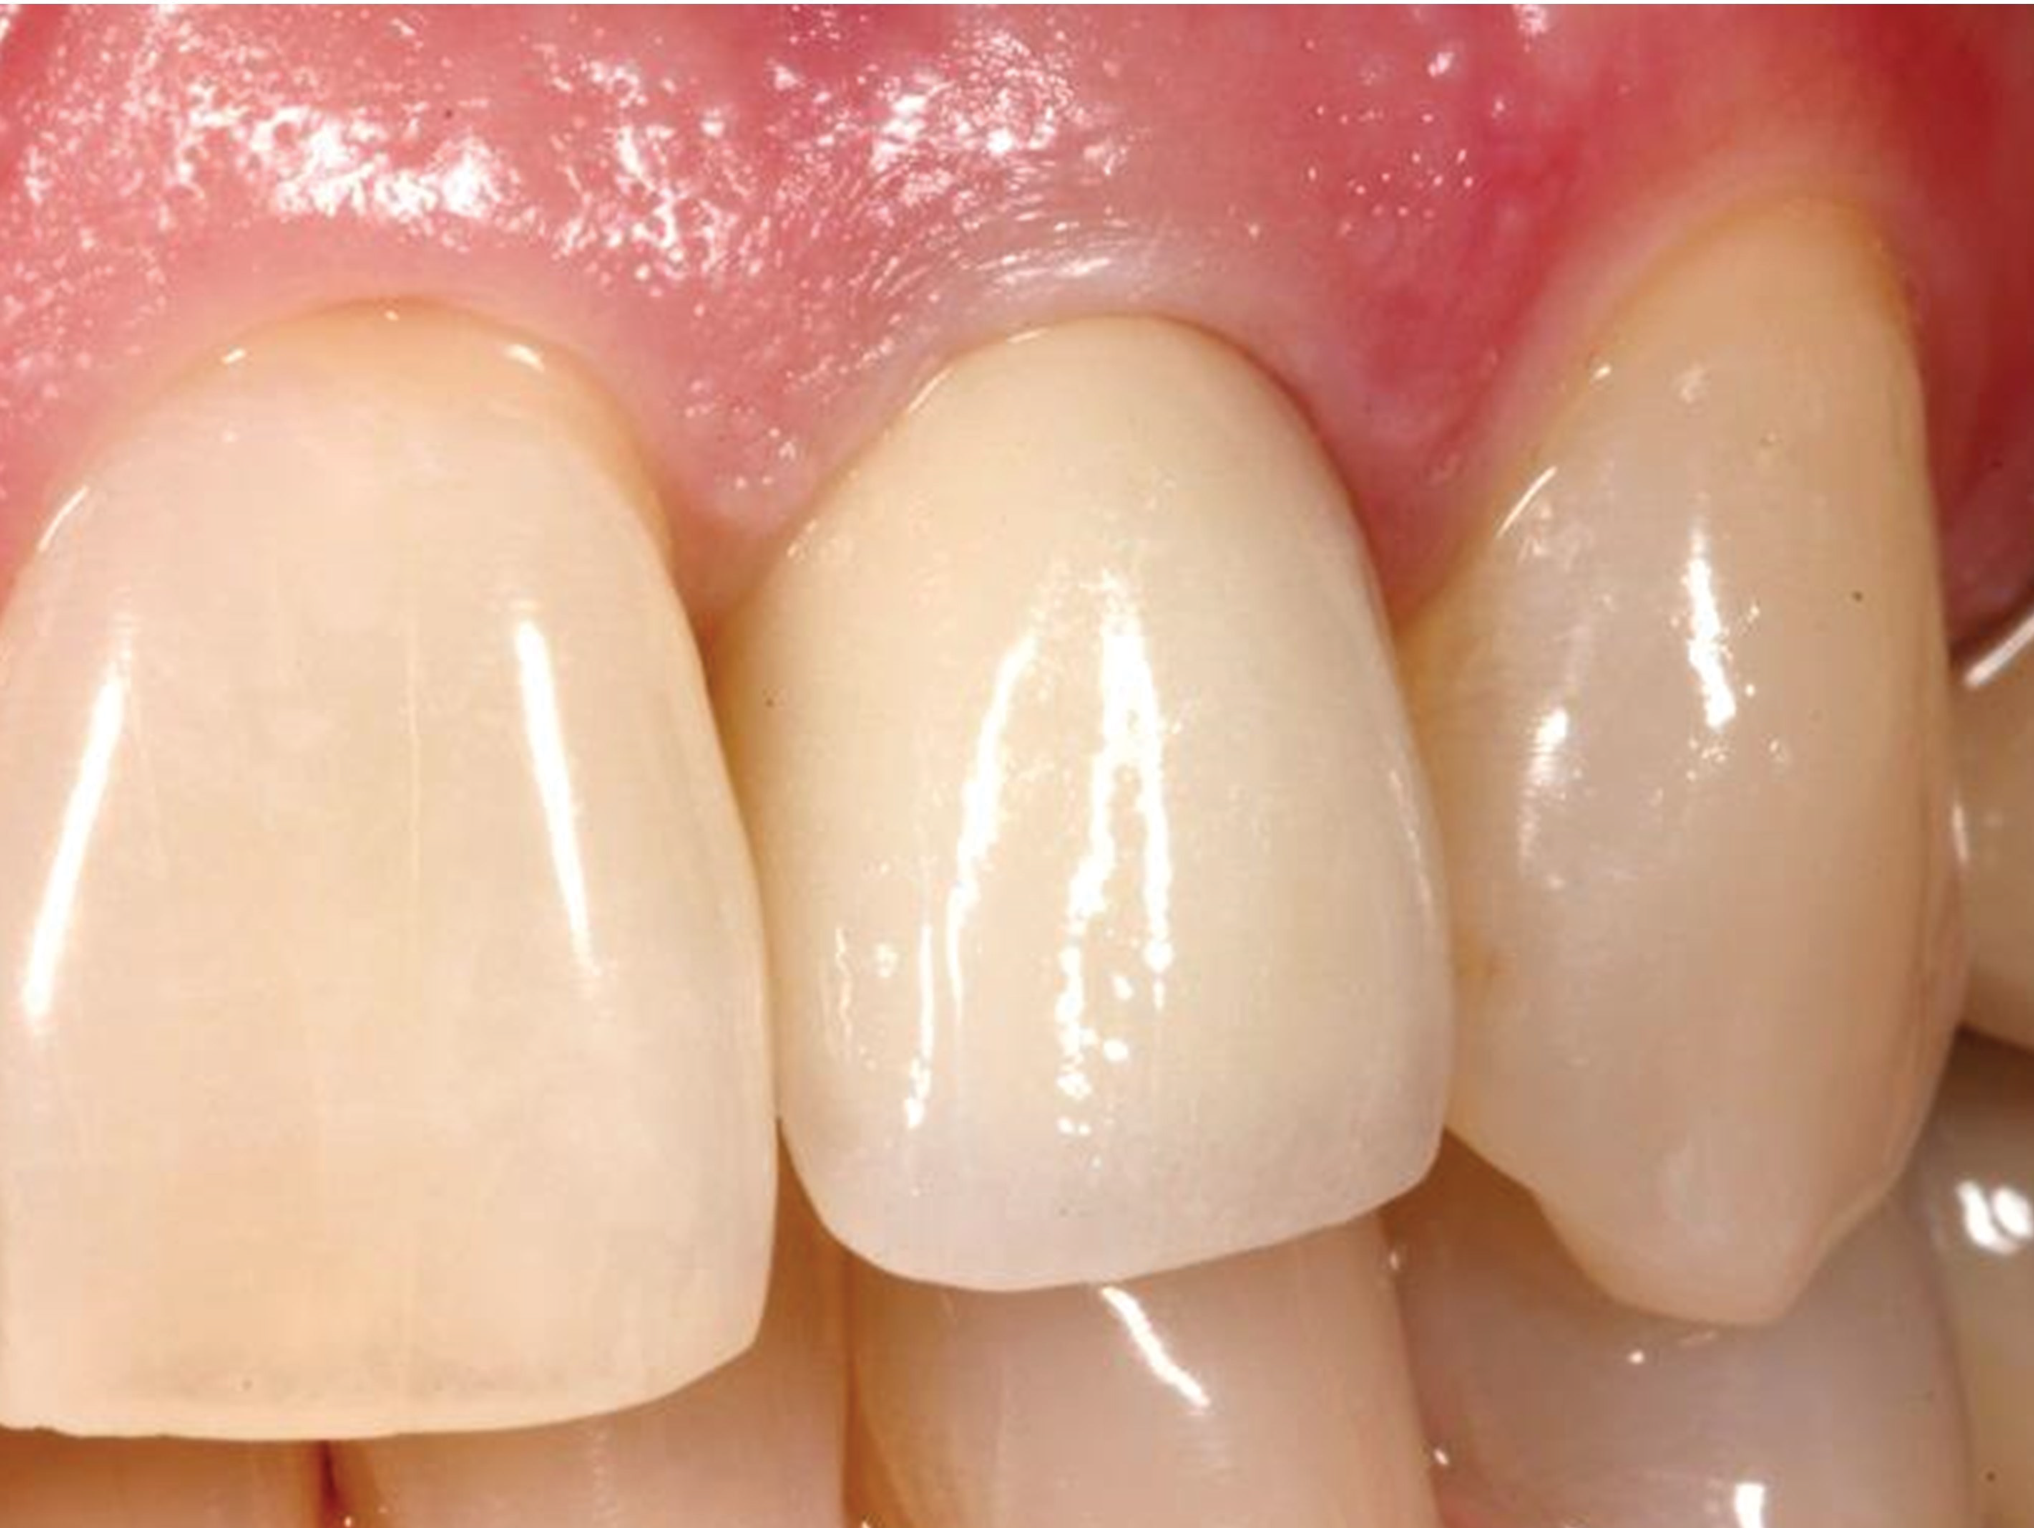

Fig 15. The provisional crown removed to demonstrate the ideal appearance of the soft-tissue contour prior to permanent crown insertion.

Figure 15

Fig 16. The permanent crown after 16 months in place.

Figure 16